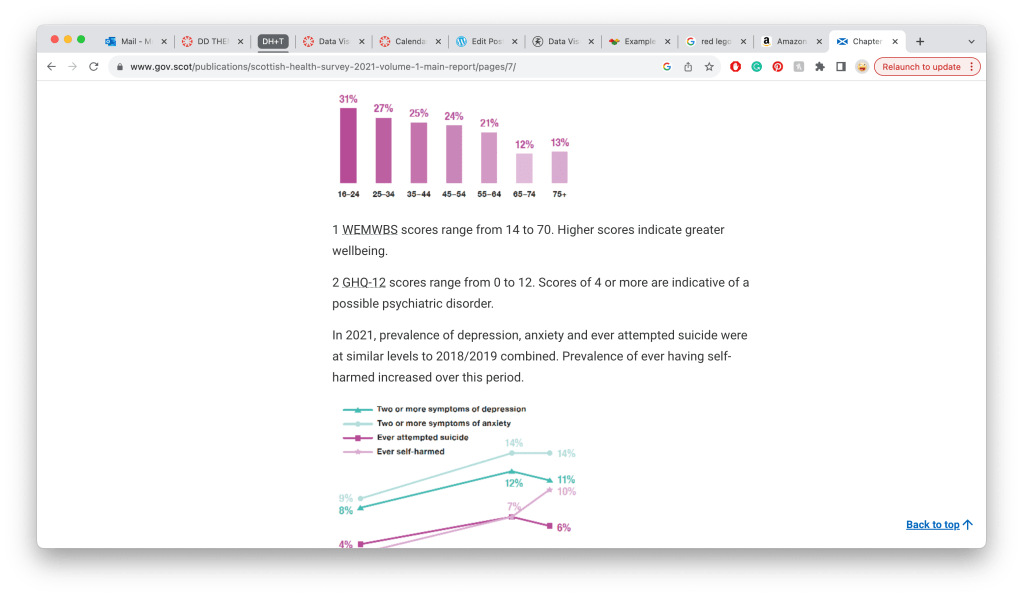

https://www.gov.scot/publications/scottish-health-survey-2021-volume-1-main-report/pages/7/